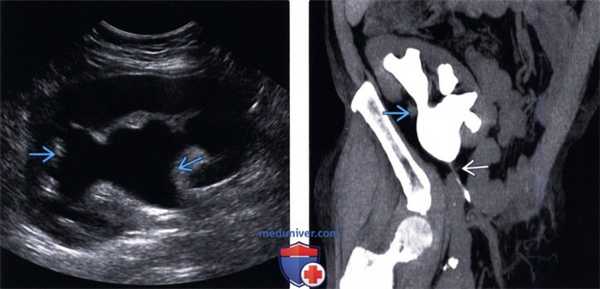

(Левый) На продольном УЗ срезе трансплантата почки визуализируется взвесь в расширенной почечной лоханке. У пациента после чрескожной биопсии появилась макрогематурия. В такой ситуации необходимо исключить артериовенозную фистулу.

(Правый) На поперечном УЗ срезе мочевого пузыря с цветовой допплерографией у того же пациента с гематурией после биопсии трансплантата почки в мочевом пузыре визуализируется крупный аваскулярный тромб.

(Левый) На поперечном УЗ срезе с цветовой допплерографией визуализируется конкремент, приводящий к гидронефрозу трансплантата почки легкой степени. Конкремент вызывает артефакт мерцания и заднее акустическое затенение.

(Правый) На чрескожной нефростомограм-ме визуализируется расширенная почечная лоханка и сдавленные чашечки. Визуализируется обтурирующий конкремент в виде округлого дефекта наполнения. В нерасширенном мочеточнике дистальнее конкремента и в мочевом пузыре визуализируется контраст.